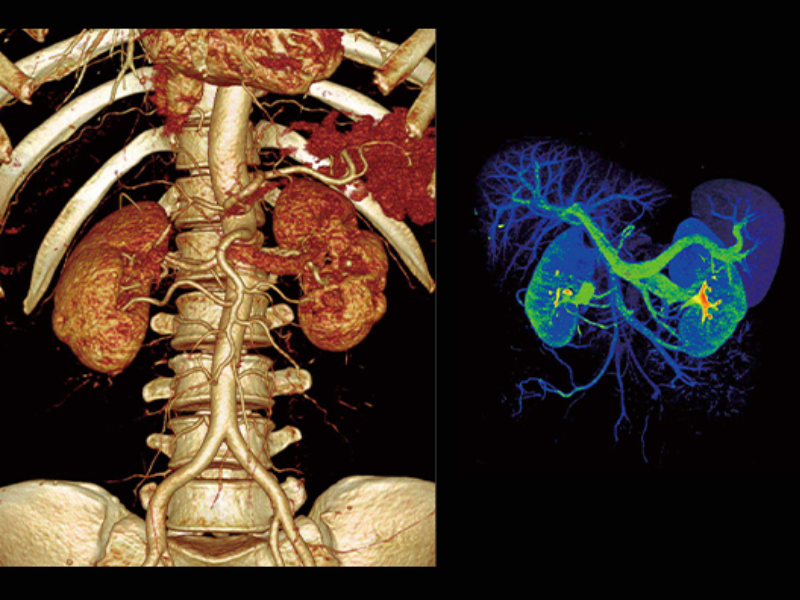

Ultra-Fast High-Resolution Imaging

The large 30 cm axial digital PET field of view (FOV) with 2.9 mm NEMA resolution and the 160-slice CT with 0.25 mm isotropic spatial resolution improves quantitative accuracy and small lesion detectability.

High Resolution PET

Whole Organ Coverage

Small Lesions Detectability with Gallium-68